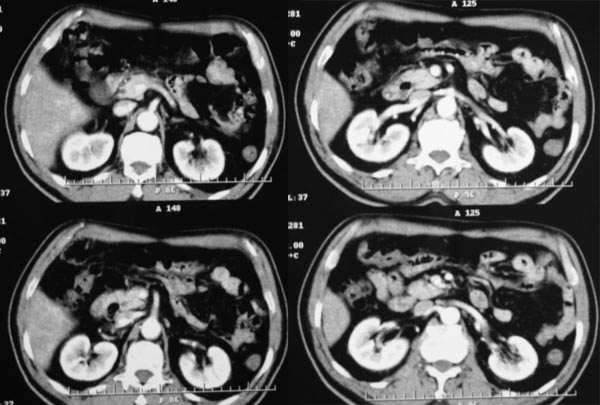

动脉期

2、动脉期:病灶边缘强化明显,明显高于肝实质,中间未强化为坏死区

3、门脉期:病灶呈低密度,低于肝实质,下腔静脉见充盈缺损,说明癌栓形成

2.病灶特点:平扫呈低密度,密度不均,中央呈更低密度;动脉期病灶周围强化较明显,高于正常肝组织,低于同层主动脉密度,中央坏死区未见明显强化;门静脉期,病灶呈低密度,低于正常肝组织密度。

肿瘤实质的强化特点符合肝癌表现,需要注意的地方还有患者可能存在门脉右支和下腔静脉内癌栓形成,这更加支持肝癌的诊断。

肿瘤的生长特点和强化特点符合纤维板层样肝细胞癌,下腔静脉内在动脉期有充盈缺损,而在静脉期内未见充盈缺损,故不考虑下腔静脉瘤栓形成